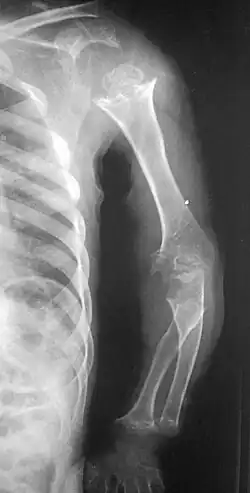

Pseudoachondroplasia. Shoulder and humerus. Note the dysplastic proximal humeral epiphysis, metaphyseal broadening, irregularity and metaphyseal line of ossification. These changes are collectively known as "rachitic-like changes". Lesions are bilateral and symmetrical. | |

Skeletal radiography

Accurate assessment of plain radiographic findings remains an important contributor to diagnosis of pseudoachondroplasia. It is noteworthy that vertebral radiographic abnormalities tend to resolve over time. Epiphyseal abnormalities tend to run a progressive course. Patients usually suffer early-onset arthritis of hips and knees. Many unique skeletal radiographic abnormalities of patients with pseudoachondroplasia have been reported in the literature.[2][7][4]

- Dysplastic/hypoplastic epiphyses especially of shoulders and around the knees.

- Metaphyseal broadening, irregularity and metaphyseal line of ossification. These abnormalities that are typically encountered in proximal humerus and around the knees are collectively known as "rachitic-like changes".

- Radiographic lesions of the appendicular skeleton are typically bilateral and symmetric.